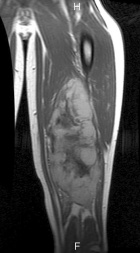

J.G. - 14 year old male c/o left posterior thigh mass for eight months. His mother noticed the mass, but no ecchymosis, after he fell while running hurdles. He complains of pain only when running long distances, and with prolonged pressure. It has decreased in size only minimally. No F/C.